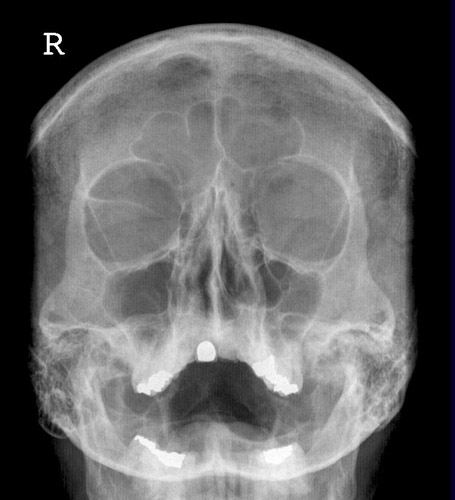

Schädel/Gesicht

Schädel a.p.

Fehler

Schräge Projektion, d.h. ungleicher Seitenabstand der Schädelkapsel vom Keilbeinflügel.

Abhilfe

Symmetrische Lagerung des Kopfes.